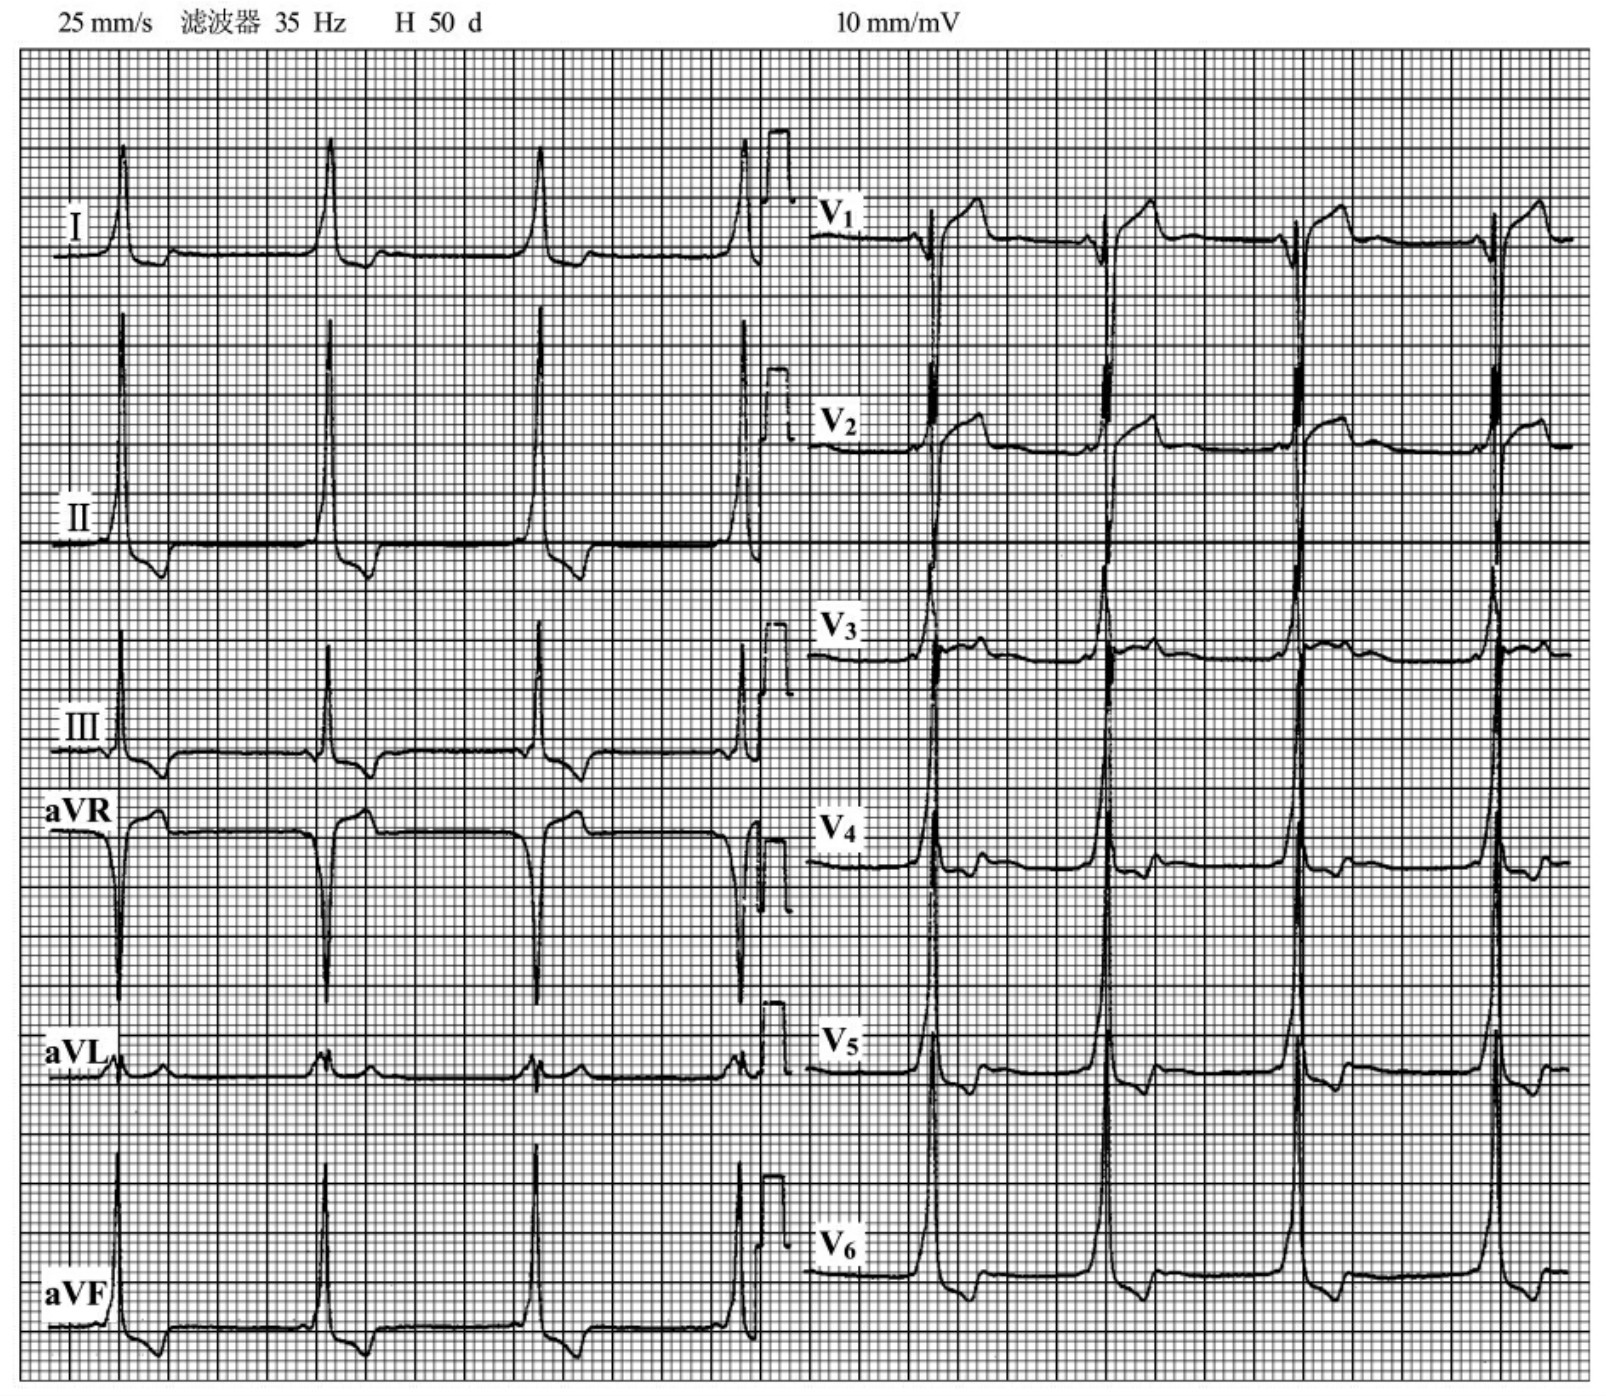

img1013

图45-19 患者男性,45岁,心肌病史,心电图QRS波增宽(0.13s),Ⅱ、Ⅲ、a VF、V4~V6导联均可见异常Q波